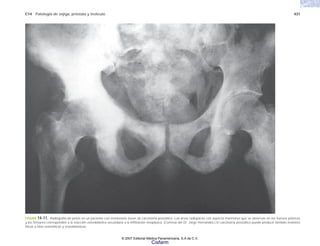

crisis convulsivas, o muerte de la madre y el niño du-

rante un parto. La enfermedad seguía siendo la misma,